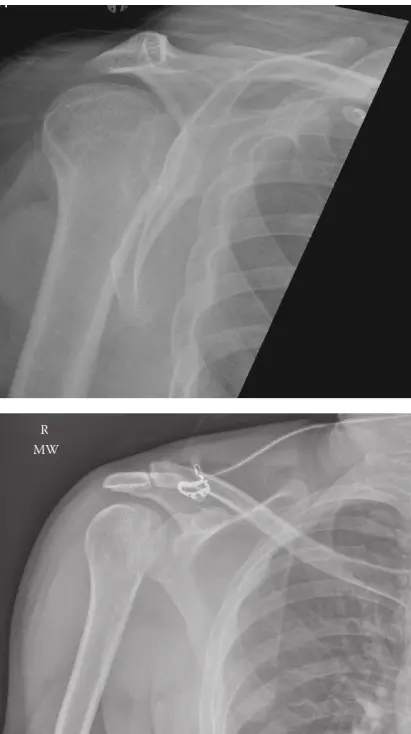

صورة توضيحية لـ الخلع الخلفي لمفصل الكتف: دليل شامل للمرضى من التشخيص إلى التعافي

• "علامة الضوء اللمبة" (Light Bulb Sign) في الأشعة السينية: وهي علامة إشعاعية مميزة سنتحدث عنها لاحقًا.